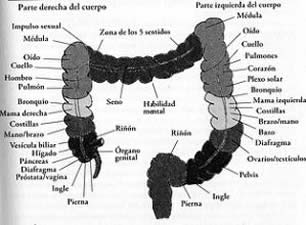

Además, en el colon se localizan terminales nerviosas o puntos reflejos, que inciden en otros sistemas:

- En el sistema nervioso, con el cerebro y la médula espinal como sus piezas principales, que envían señales a otros sistemas del cuerpo para controlar su funcionamiento.

- En el sistema cardíaco, con el corazón y los vasos sanguíneos como protagonistas, que se encargan de transportar sangre con oxígeno y nutrientes hacia todas las células del organismo y de llevar los desechos de éstas hacia los pulmones

- En el sistema endocrino que secreta hormonas, desde distintas glándulas, para que actúen en células específicas que propiciarán un efecto deseado en el organismo.

- Cada sistema y órgano del cuerpo está conectado al colon por puntos reflejos.

- Cada sesión de hidroterapia de colon estimula estos puntos reflejos, accionando las partes del cuerpo correspondientes, de una manera beneficiosa similar a la reflexología.